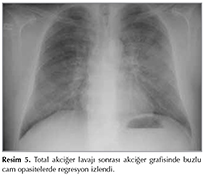

PAP tanısı ile istirahatte nefes darlığı ve hipoksemisi olan hastaya genel anestezi altında total akciğer lavajı planlandı. İlk seansda ameliyathanede ?ift l?menli endotrakeal t?p yoluyla sol akciğer yukarıda kalacak şekilde hasta lateralde k?bit pozisyona getirilerek total akciğer lavajı uygulandı. Sol akciğere her seferinde 500 cc ısıtılmış (37?C) serum fizyolojik (SF, %0.9 NaCl) verildi, ara ara t?p klemplenerek, g?ğ?s perk?syonu yapıldı ve sonrasında hasta trandelenburg pozisyonuna getirilerek sıvı boşaltıldı. Gelen sıvı berraklaşıncaya kadar işleme devam edildi ve toplam dokuz litre SF kullanıldı (Resim 4). İşlemle ilgili herhangi bir komplikasyon gelişmedi. Hastaya iki g?n sonra aynı işlem sağ akciğer i?in uygulandı ancak bu kez toplam 20 litre SF kullanıldı. İşlemle ilgili herhangi bir komplikasyon gelişmeyen hasta 48 saat g?zlem sonrasında taburcu edildi. On beş g?n sonraki kontrol akciğer radyogramında buzlu cam opasitelerde belirgin regresyon mevcuttu (Resim 5). Kontrol 6 dakika y?r?me testinde belirgin iyileşme (mesafe, bitiş saturasyonu) saptandı (başlangı? SpO2 %97, bitiş SpO2 %92, 396 metre y?r?d?). İşlemden d?rt ay sonra ?ekilen kontrol YRBT'de sağ akciğer ?st lobda, orta lob lateral segmentte ve alt lobda, sol akciğer ?st lobda ve alt lob mediobazal segmentte buzlu cam dansiteleri ve interlob?ler septal kalınlaşma izlendi ve hastanın ?nceki akciğer YRBT tetkiki ile karşılaştırıldığında akciğerdeki lezyonlarda belirgin regresyon saptandı (Resim 6). Hasta halen 12 aydır ek tedavi uygulanmaksızın klinik ve radyografik olarak stabil takip edilmektedir.

Resim 5